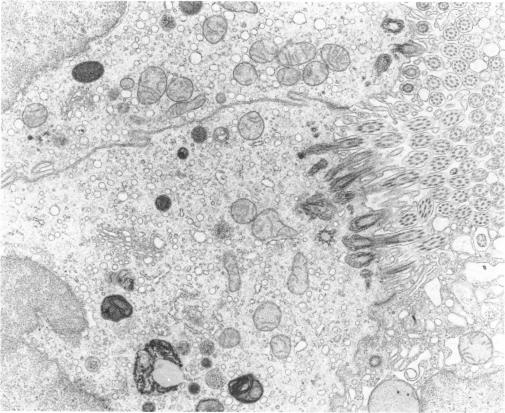

Neoplastic and nonneoplastic effects of vinyl chloride in mouse lung

Source:Environ Health Perspect. 41:31-52.